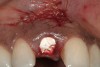

A 34-year-old woman presented with a chief complaint of mild discomfort and swelling associated with the maxillary left lateral incisor. The patient reported a history of root canal therapy and crown performed approximately 10 years earlier. Findings from the clinical examination revealed a localized buccal gingival swelling at the level of the mucogingival junction distal to the lateral incisor, with a 9-mm probing depth on the direct facial of the tooth (Figure 1 ). Observations from the radiographic examination demonstrated a periradicular radiolucency but suggested normal interdental bone levels (Figure 2 ). Surgical exposure following flap elevation exposed a 10-mm dehiscence defect of the buccal plate (Figure 3 ), which was consistent with a vertical root fracture and hopeless prognosis. The lateral incisor was extracted to minimize the loss of alveolar bone and this was followed by thorough degranulation of the socket. Particulate FDBA saturated with rhPDGF-BB for 10 minutes was then applied to augment the deficient ridge in preparation for future implant placement (Figure 4 ). The extraction site was developed to approximate the contours of the adjacent alveolar ridge. Then, a resorbable collagen membrane (Bio-Gide®, Osteohealth) was placed over the graft to facilitate graft containment and maintenance of desired alveolar contours (Figure 5 ). Placement of the membrane without disruption or displacement of the graft during completion of the surgical procedure and suturing is critical to ensure clot formation that will support bone formation.

Figure 4   Extraction socket and ridge defect augmented with particulate freeze-dried bone allograft (FDBA) saturated with rhPDGF.

Figure 4